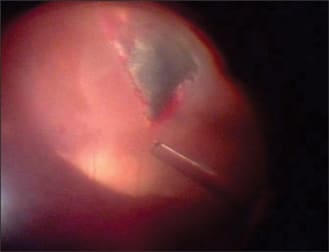

A 20-year-old male sustained an intraocular foreign body (IOFB) in his left eye by hitting a hammer against a large metallic object. He presented to the emergency room 1 day after the injury. On examination, his visual acuity was 20/200, and a large nasal conjunctival hemorrhage was observed with hypotony and clear cornea and lens. On indirect funduscopy, a metallic intraocular foreign body was observed stuck in the inferior retina at the equator with a local retinal detachment, whitening of the retina around its edges, and a mild vitreous hemorrhage. The intraocular foreign body was demonstrated on orbital CT (Figure 1). An exploration revealed a 4 mm entry wound, extending posteriorly from the limbus at the nasal side. The wound was sutured with Vicryl 7/0 suture, an encircling #41 solid silicone band was placed (Figure 2), and a pars plana vitrectomy was performed during the primary procedure. The intraocular foreign body was released from its adhesions to the retina (Figure 3) and removed with a magnet (Figure 4) through a previously prepared sclerotomy, revealing a large retinal tear (Figure 5). The intraocular foreign body outside the eye is shown in Figure 6.

Figure 3. Intraoperative view of the IOFB, local retinal detachment, and retinal whitening.